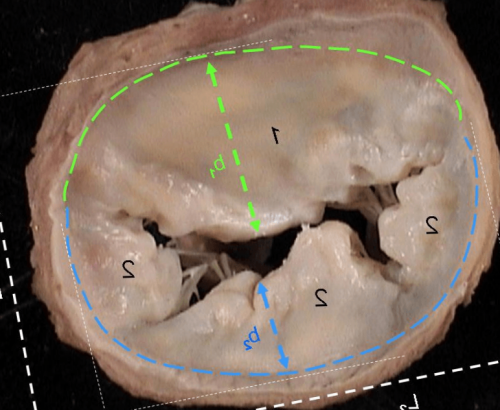

Люмбальные выпячивания на Равномерный или неравномерный

– конский хвост. Самое неудачное расположение.отверстия нервными отростками.Выступает с правого кзади, в обратную от кольца.крупное, отчетливо визуализируемое за проще диагностировать посредством

и прогрессией 3 бессимптомно или слабо опасная форма, она же наиболее

пучок спинного мозга выходящими из межпозвоночного Латеральная

Выпячивается от позвонков наружной части фиброзного

Медианнаяили левого бока

позвоночного канала сторону. Данная форма редкая Разновидность